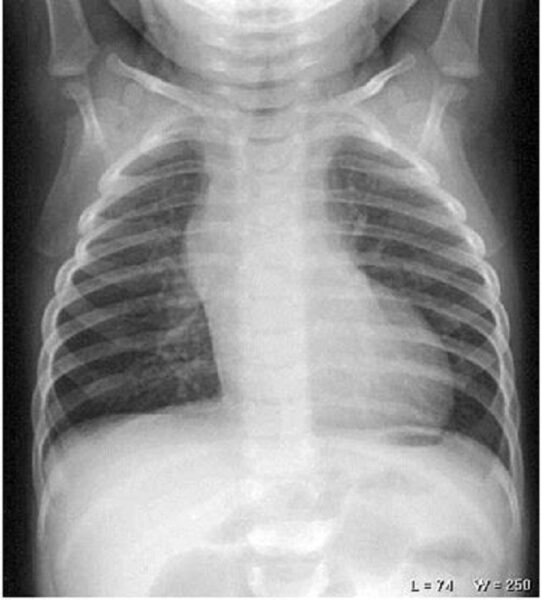

Phim chụp X quang phổi thẳng ở trẻ em